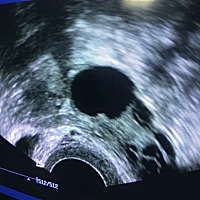

大卫验到这样,是不怀孕了